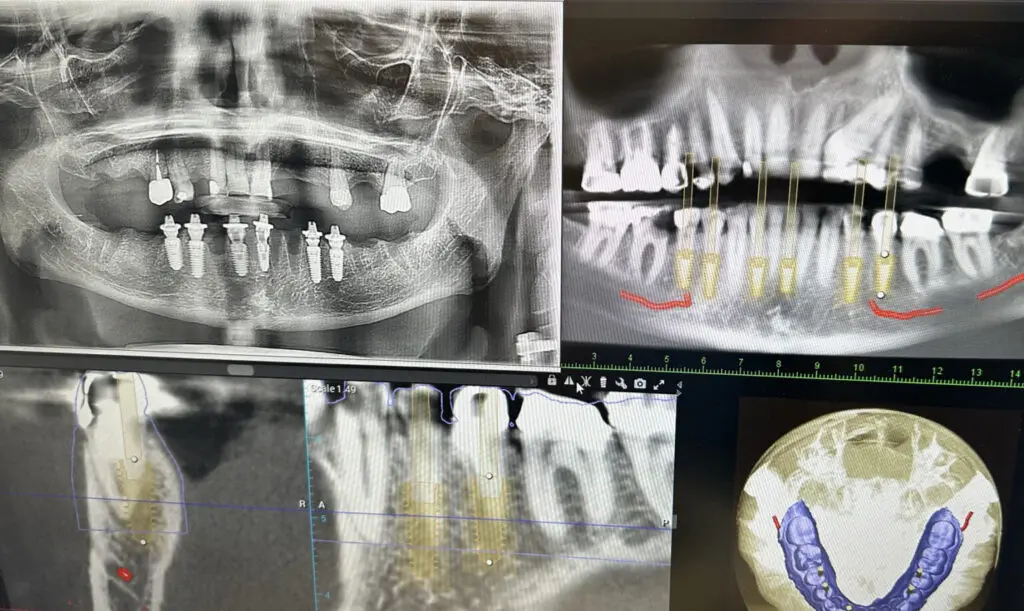

CBCT Scanning

Cone-beam computed tomography (CBCT) produces a detailed 3D x-ray of your mouth and teeth that we can use for evaluation and treatment planning. This detailed offers a better reference as we determine treatment needs, and it can reveal potential complications we can plan around and resolve more easily. 3D scans are useful in treating alignment issues, and they provide better information to prepare for dental implant placement.